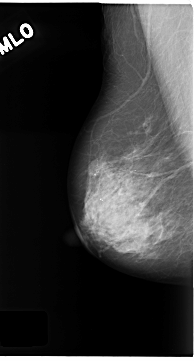

C_0180_1.RIGHT_MLO

RIGHT_MLO LINES 4688 PIXELS_PER_LINE 2520 BITS_PER_PIXEL 12 RESOLUTION 50 NON_OVERLAY